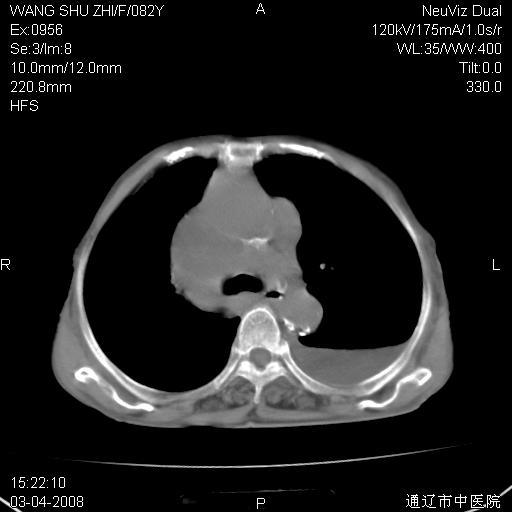

该患者为女性,82岁,既往肺心病、心衰病史。上纵隔影增宽,是否为畸形扩张的血管呢?因该患者年龄太大,又有较严重心脏病,故不适宜做增强检查。

中纵隔肿块最多见是淋巴瘤,而且以hd为多见,呈侵袭性生长,纵隔脂肪间隙消失,再加上心包和双侧胸腔积液,考虑为淋巴瘤(hd)应该说比较准确的。至于说是畸形的血管可能性小,因为畸形血管周围脂肪间隙应该存在。

纵隔淋巴结转移或淋巴瘤;双侧胸腔积液,心包积液。肺窗呢?

左侧腋窝及纵隔内见多个肿大淋巴结影,左侧少量胸腔积液,心包积液,支持淋巴瘤可能性大,不除外淋巴结转移。